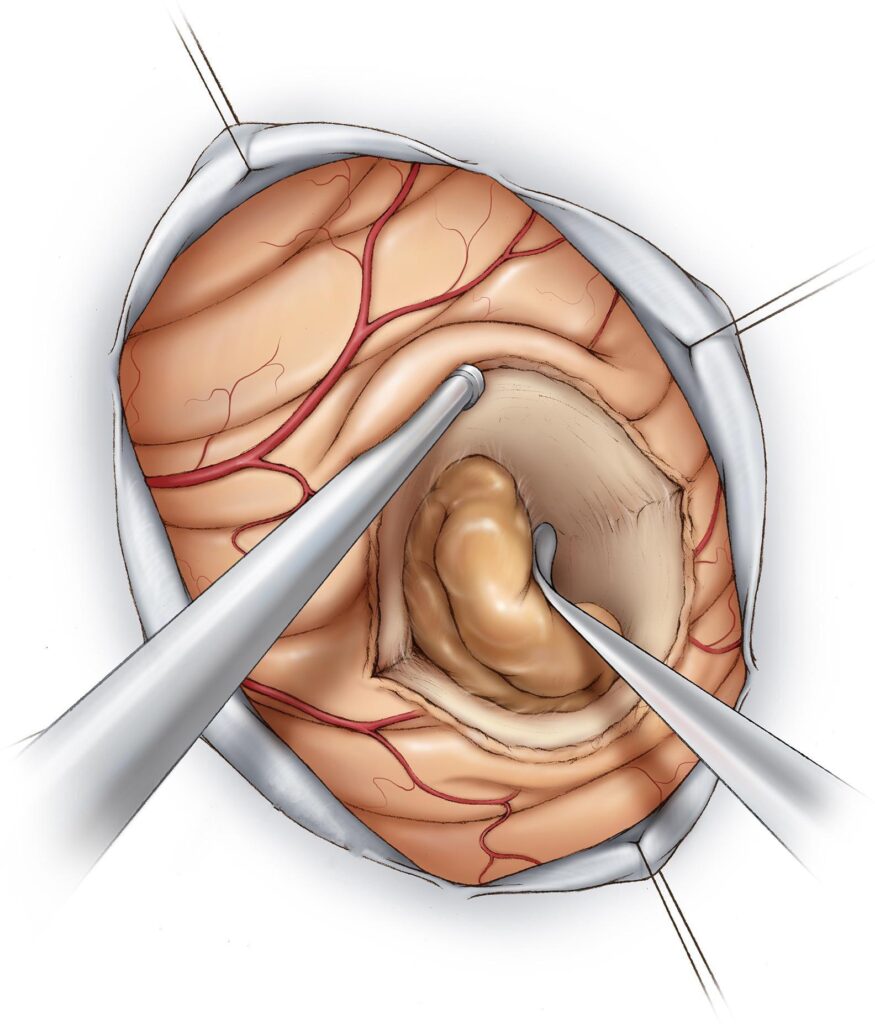

Cirurgia

- Indicações:

- remoção de massas sintomáticas.

- estabilização espinhal em casos de compressão medular.

RESSECÇÃO NEUROCIRÚRGICA DE METÁSTASE CEREBRAL